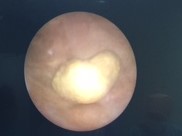

The Miniaturization of Instruments and Laser Lithotripsy have Improved Urolithiasis Treatment without Requiring Fluoroscopic Control in Preschool Children

Fazlı Polat, Zafer Turkyilmaz, Ramazan Karabulut, Suleyman Yesil, Kaan Sonmez